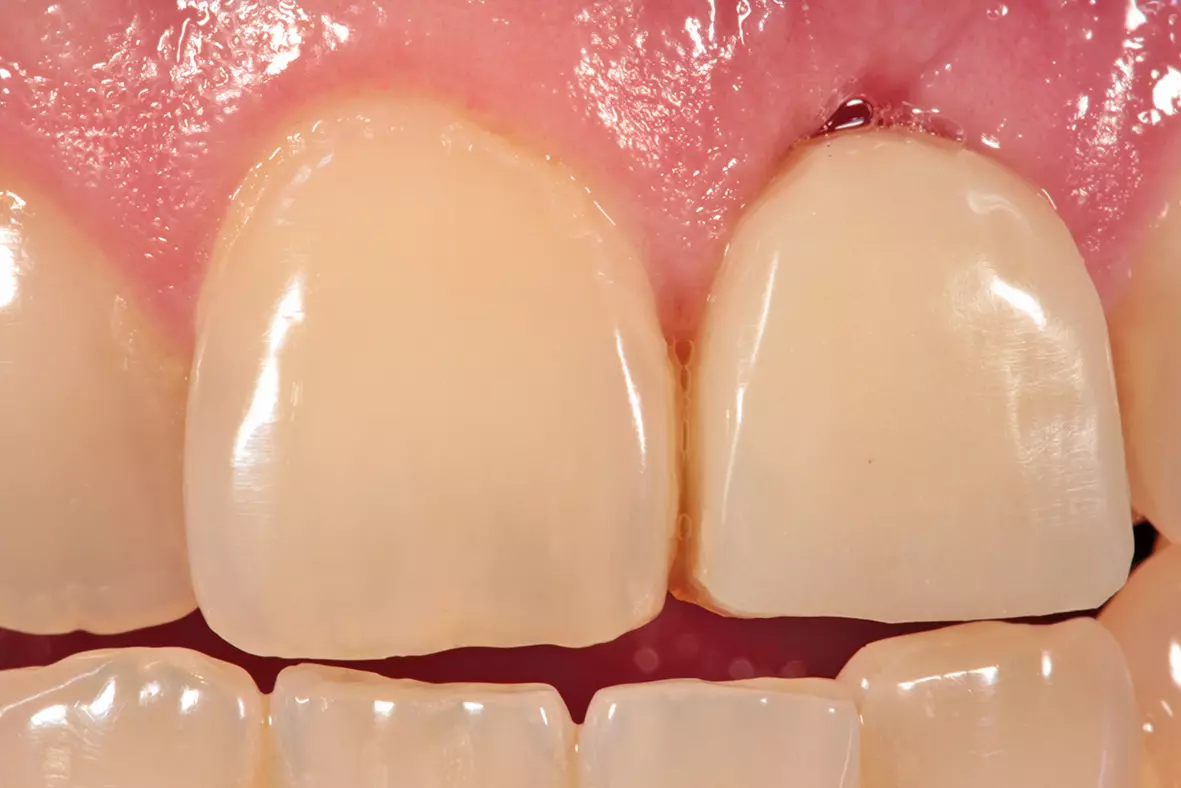

Nach drei Monaten folgte die Freilegung (Abb. 17). In der Operation erfolgte zunächst unter dem Mikroskop wieder die krestale Schnittführung an derselben Stelle wie bei der Implantation unter Erhalt eines einige Millimeter breiten Streifens befestigter Mukosa. Dann wurde der Lappen mit einem Papillenraspatorium zuerst etwas angehoben und dann scharf epiperiostal weiterpräpariert. Die Verschlussschraube wurde aus dem Implantat entfernt und die provisorische Krone eingegliedert. Der interdentale Wundverschluss erfolgte mit Prolene 6.0 (Ethicon, Johnson & Johnson Medical) in Form von vertikalen Matratzennähten (Abb. 18).

Fertigstellung und Eingliederung der definitiven Krone

Im Anschluss wurde die Zirkonkrone mit Hilfe von Individualmassen (Creation ZI CT Firma Willi Geller) individualisiert und verblendet (Abb. 25 und 26). Nach Fertigstellung der Krone wurde sie mithilfe von Multilink Implant und Monobond Plus (Ivoclar Vivadent) mit einer Titanbasis für CAD/CAM (Thommen Medical) verklebt. Vom Zahnarzt wurde die provisorische gegen die definitive Krone ausgetauscht (Abb. 27).

Mithilfe dieser Technik war es möglich, den ursprünglichen Wurzeldurchmesser zu erhalten und nicht über eine lange zeitaufwändige Ausformung neu gestalten zu müssen.